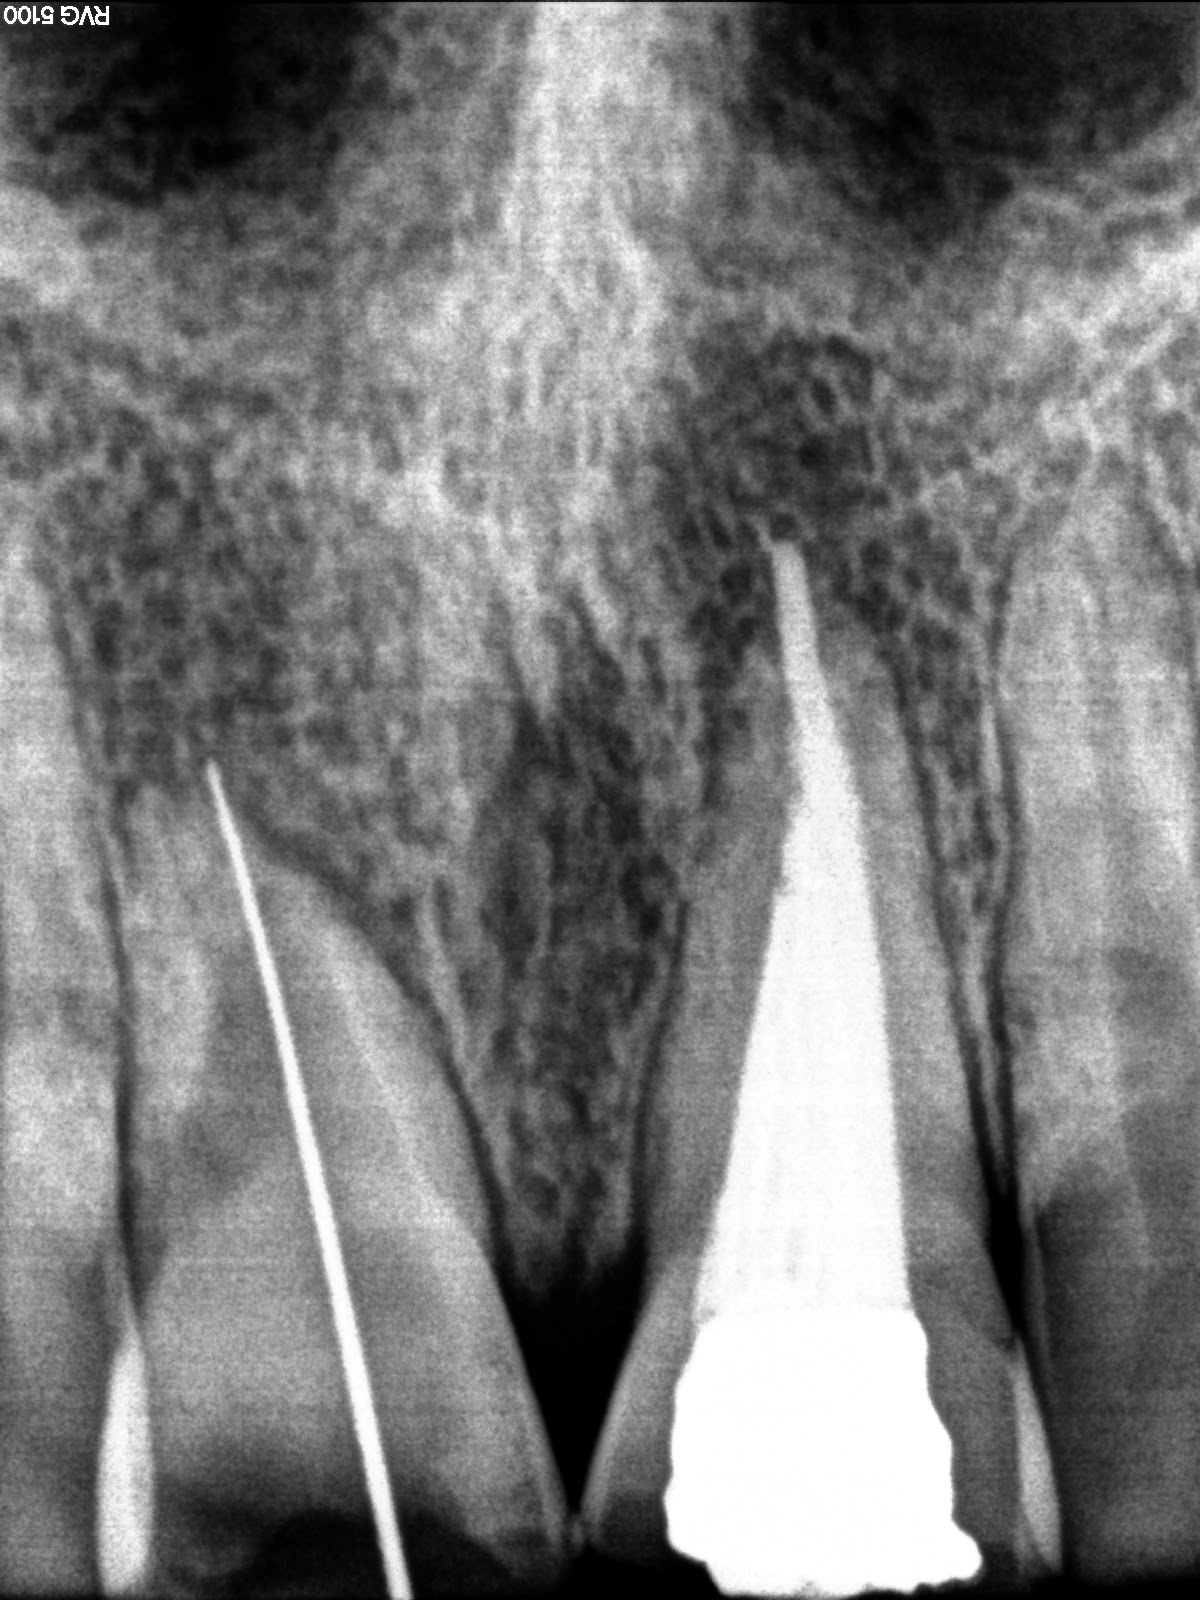

Live Steps Root Canal Rotary Protaper Endodontic Procedure ACP, BMP

From www.dentalclinic-knet.com

Live Steps Root Canal Rotary Protaper Endodontic Procedure ACP, BMP What Is Obturation In Dentistry Within endodontics, many dentists are highly skilled in obturation. That is down to how well you clean the canal and eliminate bacteria. Obturation is a step of the root canal procedure during which the pulp chamber is filled and sealed with gutta percha. Learn about obturation from a clinician’s guide to clinical endodontics dental ce course & enrich your knowledge. What Is Obturation In Dentistry.